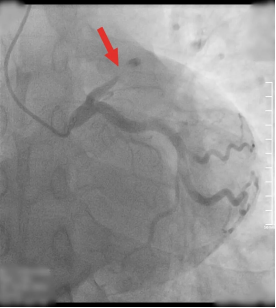

● 冠脉CTA(冠状动脉CT血管造影):该项检查可以判断血管的狭窄程度或者堵塞。

心导管术:该项检查可以显示出心脏中的任何动脉是否堵塞。